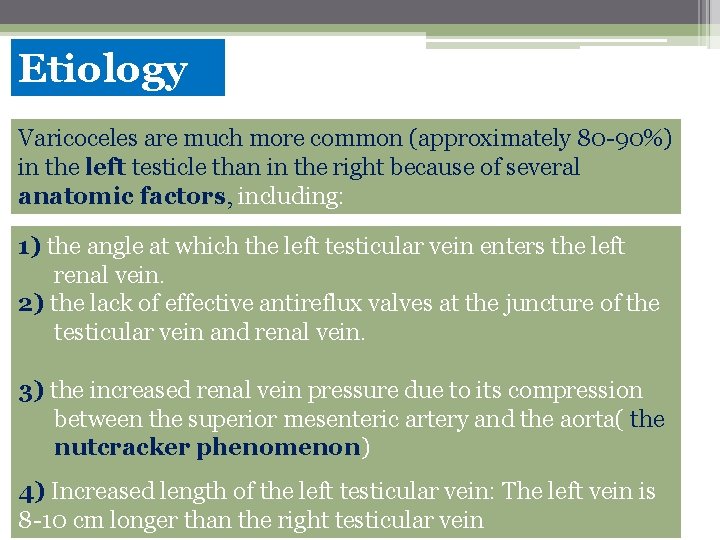

Etiology Varicoceles are much more common (approximately 80 -90%) in the left testicle than in the right because of several anatomic factors, including: 1) the angle at which the left testicular vein enters the left renal vein. 2) the lack of effective antireflux valves at the juncture of the testicular vein and renal vein. 3) the increased renal vein pressure due to its compression between the superior mesenteric artery and the aorta( the nutcracker phenomenon) 4) Increased length of the left testicular vein: The left vein is 8 -10 cm longer than the right testicular vein

80% of men with a left clinical varicocele had bilateral varicoceles revealed by noninvasive radiologic testing. Lt. spermatic vein pressure=10 mm Hg and ends in lt. renal vein which pressure =10 mm. Hg. so any strain can be detected by increase intra abdominal pressure by valsalva m. In Rt. side : Rt. spermatic vein pressure =10 mm Hg and ends in IVC which pressure =ZERO. So due to increase intra abdominal pressure not increasing pressure Over Rt. spermatic vein. Right side varicocele : We shoud consider possible retroperitoneal pathology (eg, renal cell carcinoma) As the cause of spermayic vein compression. Investigate further with approprite ultrasonography Or Ct scanning befor repairing the varicocele.